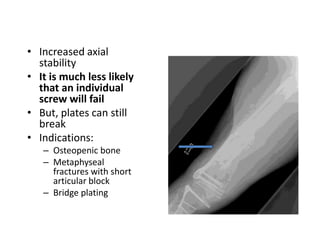

• Increased axial

stability

• It is much less likely

that an individual

screw will fail

• But, plates can still

break

• Indications:

– Osteopenic bone

– Metaphyseal

fractures with short

articular block

– Bridge plating